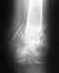

травма шейки бедра

была травма шейки бедра 2001 г. сейчас сустав стерся необходим протез .